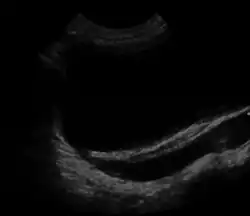

| Ultrasound image showing abnormal vesicoureteral junction and dilated distal ureter resulting in primary vesicoureteral reflux (VUR). | |

Vesicoureteral reflux (VUR), also known as vesicoureteric reflux, is a condition in which urine flows retrograde, or backward, from the bladder into one or both ureters and then to the renal calyx or kidneys.[1][2] Urine normally travels in one direction (forward, or anterograde) from the kidneys to the bladder via the ureters, with a one-way valve at the vesicoureteral (ureteral-bladder) junction preventing backflow. The valve is formed by oblique tunneling of the distal ureter through the wall of the bladder, creating a short length of ureter (1–2 cm) that can be compressed as the bladder fills. Reflux occurs if the ureter enters the bladder without sufficient tunneling, i.e., too "end-on".